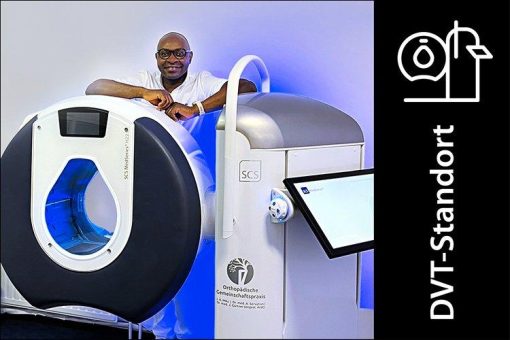

Perspektive DVT – „Schnelle Klarheit dank hochauflösender 3-D-Schnittbilder“

Herr Jones A. Mbu leitet im niedersächsischen Rotenburg (Wümme) die orthopädische Gemeinschaftspraxis, die auf die manuelle Therapie inkl. Chirotherapie, Osteopathie, FDM und Atlastherapie spezialisiert ist. Patienten können dort auf eine gründliche Diagnostik und eine ganzheitliche Therapie vertrauen. Auch operative Behandlungen, wie zum Beispiel Gelenkersatz-Operationen gehören zum Leistungsangebot. Die Ausstattung der Praxis, zu der seit AprilRead more about Perspektive DVT – „Schnelle Klarheit dank hochauflösender 3-D-Schnittbilder“[…]